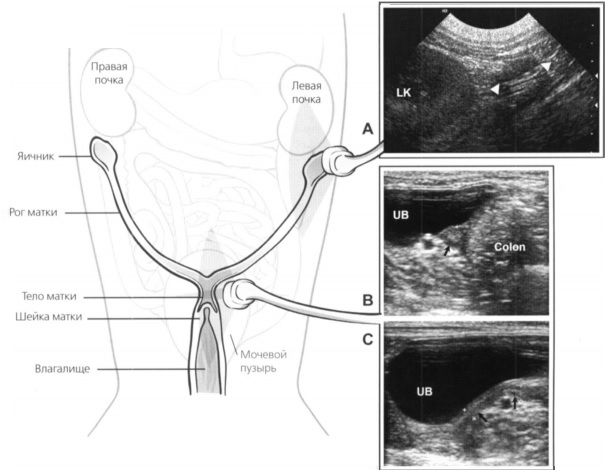

В норме матку у небеременного животного выявить сложно , часто ее трудно визуализировать у собак, и, как правило, она не видна у кошек. Лучше всего она визуализируется в каудальной части брюшной полости. В этой области она выглядит как трубчатая структура между мочевым пузырем (вентрально) и ободочной кишкой (дорсально) (Рис. 1) (источник 3). Величина и качество визуализации органа зависят от размеров животного, стадии эстрального цикла и от того, была ли ранее беременность или нет.

Рис.1 Репродуктивная система самок в норме. Яичники расположены каудально, часто латеральнее почек. Шейка и тело матки расположены дорсально от мочевого пузыря. Рога матки располагаются краниолатерально от тела матки; обычно у здоровой собаки их трудно визуализировать.А. Сканирование левого яичника у здоровой собаки (показан треугольниками) в сагиттальной плоскости. Левую почку (LK) используют в качестве ориентира, яичник выглядит как мягкотканная структура овальной формы со средней эхогенностью, расположенная каудально от каудального полюса почки. В и С. Изображение матки здоровой собаки при исследовании в поперечной (В) и сагиттальной (С) проекциях. В поперечной плоскости матка (Colon) (показана черной стрелкой) определяется как округлая структура между мочевым пузырем (UB) и ободочной кишкой, которые используют как анатомические ориентиры. В сагиттальной плоскости матка (показана черными стрелками) визуализируется как трубчатая структура средней эхогенности, расположенная дорсально от мочевого пузыря